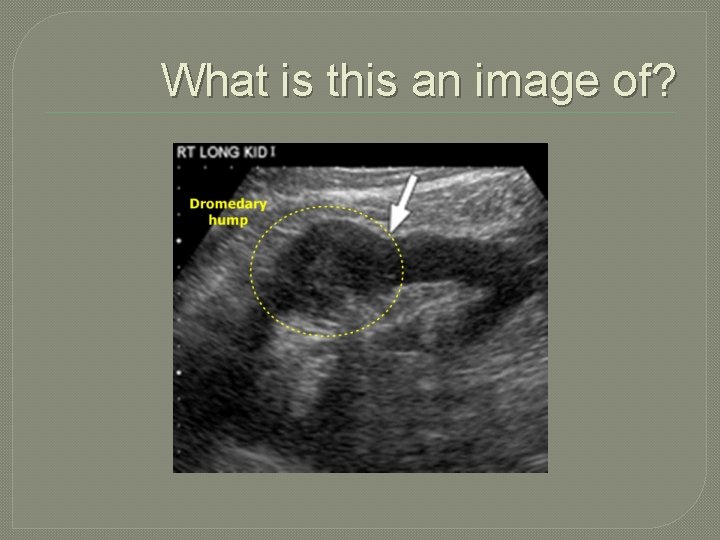

Key terms �Dromedary hump cortical bulge on the lateral aspect of the kidney. �fascia fibrous connective membrane of the body that may be separate from other structures. �Fetal lobulation immaturity of renal development resulting in a lobulated renal contour. �Gerota’s fascia protective covering of tissue surrounding each kidney.

�Renal Anatomical Variants �Dromedary hump �Cortical bulge on the lateral aspect of the kidney �Demonstrated most often on the left �Asymptomatic Lateral outward cortical bulge � Echogenicity equal to the cortex Carcinoma? � Hematoma?

What is this an image of?